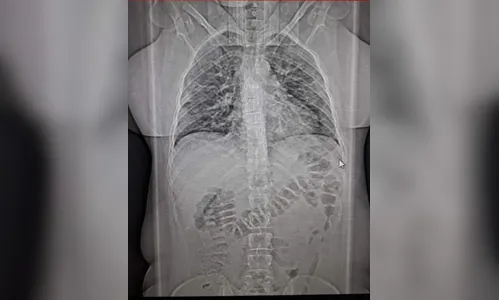

Autor Na foto, tomografia dos pulmões da sobrinha, com 60% de infecção - Foto: Arquivo pessoal

Enfim, a consulta. Suspeita de trombose. A tomografia apontou 60% dos pulmões comprometidos; os exames de sangue revelaram outras mazelas. A ordem era interná-la urgente. Eis a encruzilhada. Hospitais com corredores apinhados. Leitos, nem se cogitava.